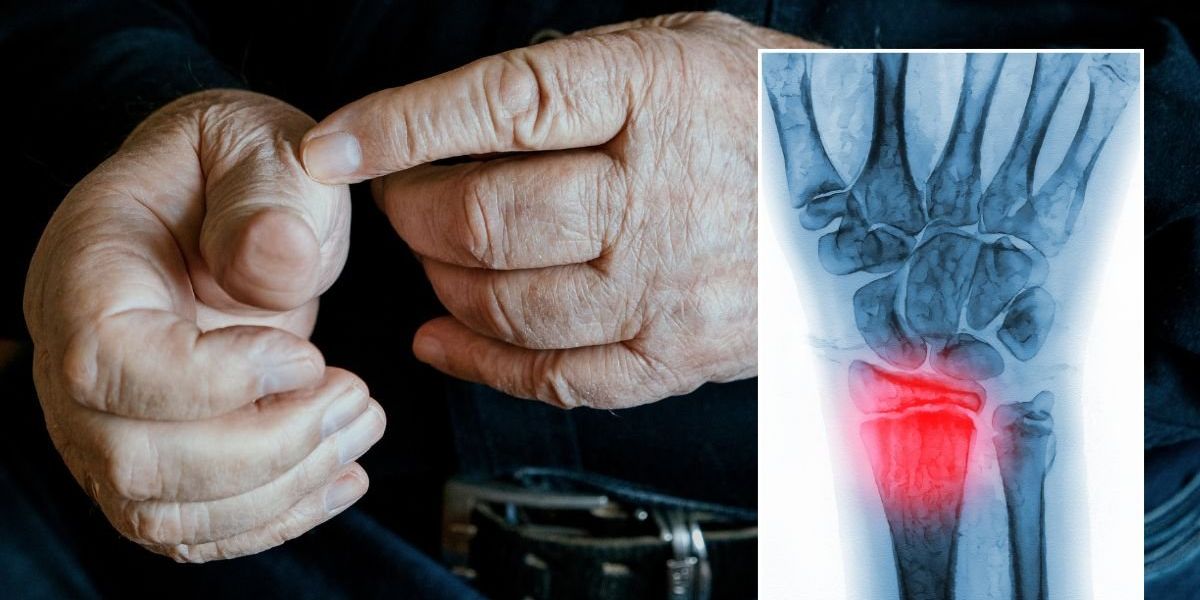

Everyday habits might be putting our bones at risk

Julia Thomson, a nurse manager at the charity, shared some insights about the hidden dangers we should all know about, highlighting how everyday habits might be putting our bones at risk.